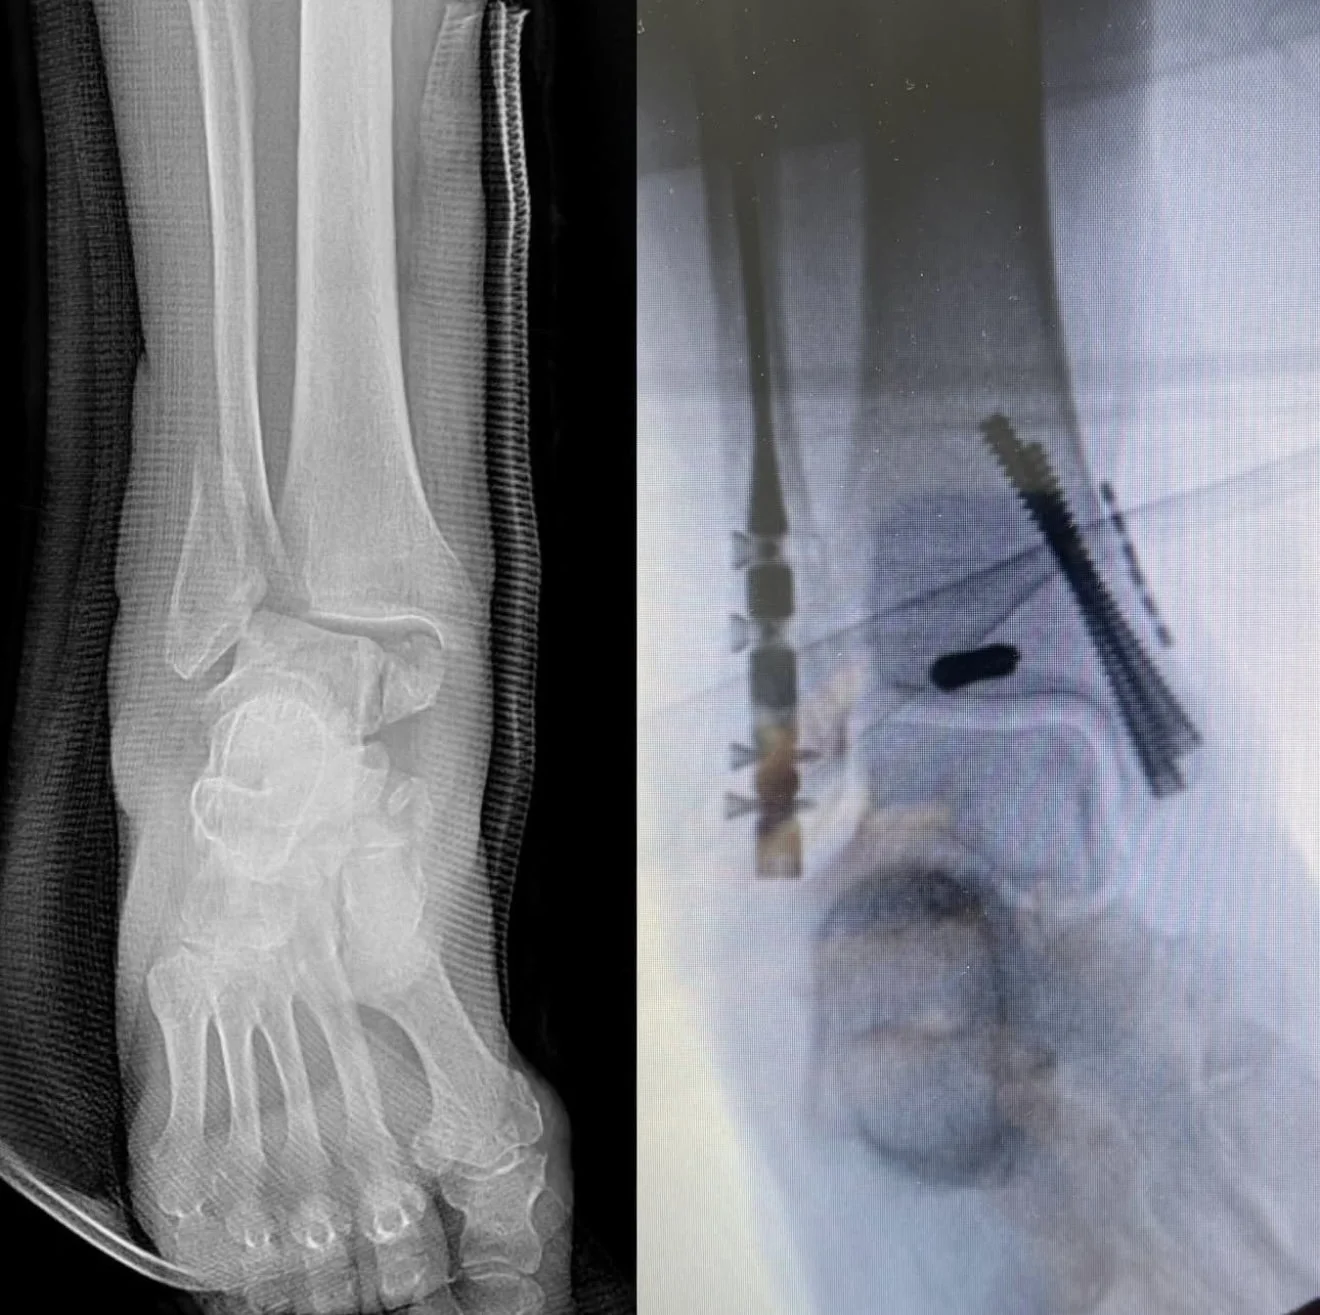

Minimally Invasive Ankle Fracture Surgery

Two X-ray images of an ankle, one shows a detailed view of the bones, and the other shows the ankle with surgical hardware and screws.